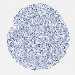

LIVER CANCER - Protein expressioni

A mouse-over function shows sample information and annotation data. Click on an image to view it in a full screen mode. Samples can be filtered based on level of antibody staining by selecting one or several of the following categories: high, medium, low and not detected. The assay and annotation is described here.

Note that samples used for immunohistochemistry by the Human Protein Atlas do not correspond to samples in the TCGA dataset.

Antibody stainingi

Antibody staining in the annotated cell types in the current human tissue is reported as not detected, low, medium, or high, based on conventional immunohistochemistry profiling in selected tissues. This score is based on the combination of the staining intensity and fraction of stained cells.

Each image is clickable and will lead to virtual microscopy that enables deeper exploration of all samples and also displays staining intensity scores, fraction scores and subcellular localization as well as patient and tissue information for each sample.

HPA048652

HPA055972

HPA055973

CAB022669

CAB047357

Staining

High

Medium

Low

Not detected

Intensity

Strong

Moderate

Weak

Negative

Quantity

>75%

75%-25%

<25%

None

Location

Nuclear

Cytoplasmic/membranous

Cytoplasmic/membranous,nuclear

Cholangiocarcinoma

Carcinoma, Hepatocellular, NOS